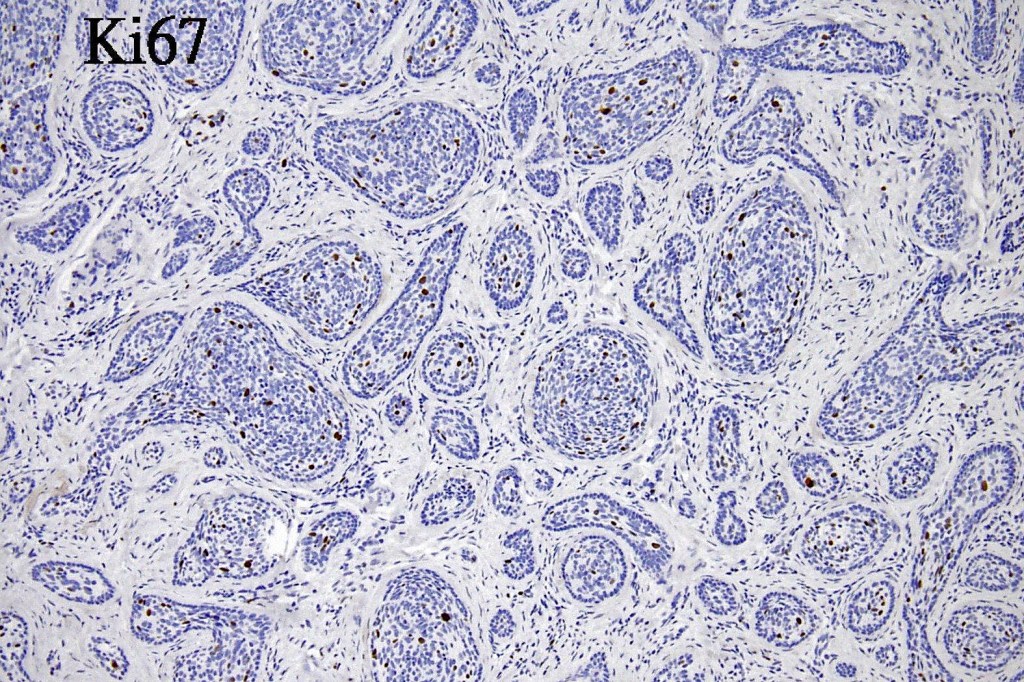

•No pleomorphism or mitotic activity

•+/- CK20 +ve Merkel cells